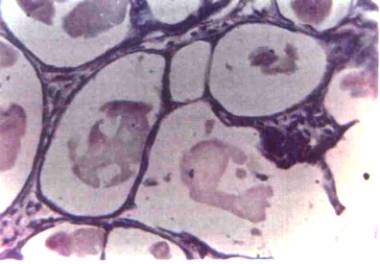

FOTOGRAFIA 5 Carcinoma ductal, variedad cribiforme. Se observa un

moderado estroma reacción y el aspecto característico dado por las Cribas o lúmenes

secundarios. 80x

FOTOGRAFIA 6 Carcinoma ductal, variedad cribiforme. Puede observarse a mayor aumento el estroma reacción, cribas características y numerosas mitosis. 300 X